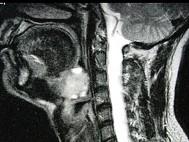

问题 女,40岁,口腔内长一肿块约九个月,逐渐感疼痛,PE:肿块呈淡红色,表面有浅溃疡,CT如图所示,最可能诊断为()

选项 A.舌根癌 B.扁桃体癌 C.扁桃体肥大 D.口底癌 E.腺样体增生

答案 A